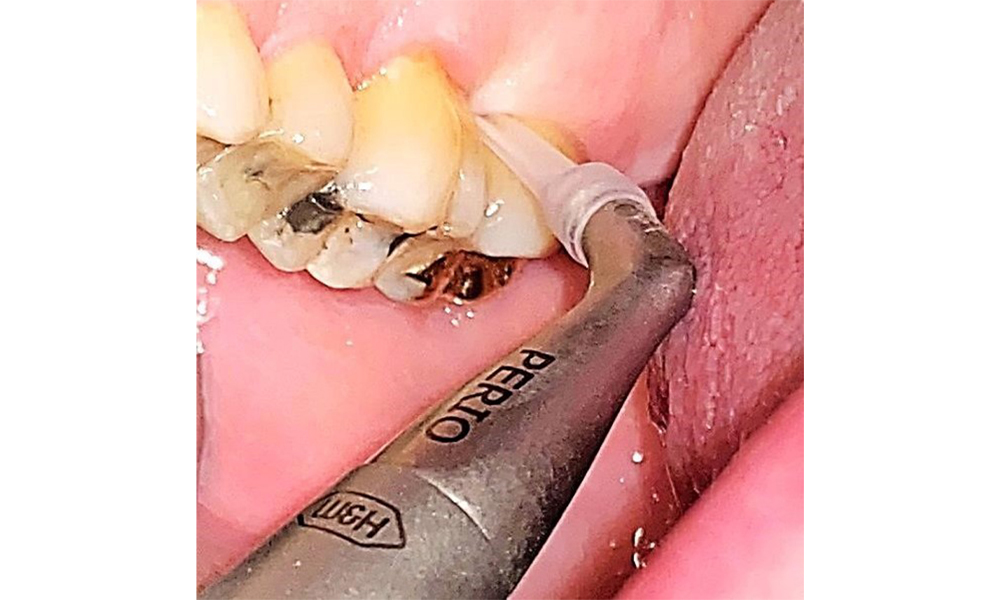

In der Instrumentierung sind bezüglich der Methodenwahl keine Einschränkungen gegeben. Aufgrund der parodontalen Vorerkrankung und dem hohen Rezidivrisikos ist die Vorbeugung einer Erkrankungsprogression durch die regelmäßige supra- und subgingivale Instrumentierung unerlässlich. Die Wahl der Instrumente zur mechanischen Biofilmentfernung ist aus allgemeingesundheitlicher Sicht nicht eingeschränkt und erfolgt bedarfsgerecht. Harte und mineralisierte Beläge wie Zahnstein und Konkremente sind mittels Handinstrumenten oder Schall/ Ultraschallscalern zu entfernen (Abb. 9) (8, 9).

Die Biofilmentfernung supra- und subgingival ist für die Stabilität des parodontalen Zustandes unerlässlich. Hier bietet sich die Methode des Air Polishing mit einem niedrig abrasiven Pulver an. Parodontale Taschen sowie freiliegende Wurzeloberflächen müssen mit niedrig-abrasiven Pulvern gereinigt werden. Für erhöhte Sondierungstiefen (tiefer als 5mm) ist eine flexible Parospitze empfehlenswert (Abb. 10). (9)

Taschentiefen bis 5mm sind auch mit einem konventionellen Aufsatz möglich (9). Die Anwendung des Pulverstrahl eines niedrig abrasiven Pulvers empfiehlt sich gleichermaßen für Restaurationsränder, Zahnzwischenräume und Fissuren. Eine rotierende Politur (Abb. 11) unterstützt durch die schonende Glättung der Oberflächen das optimale Finish der Prophylaxe und reduziert die bakterielle Wiederanhaftung (10).